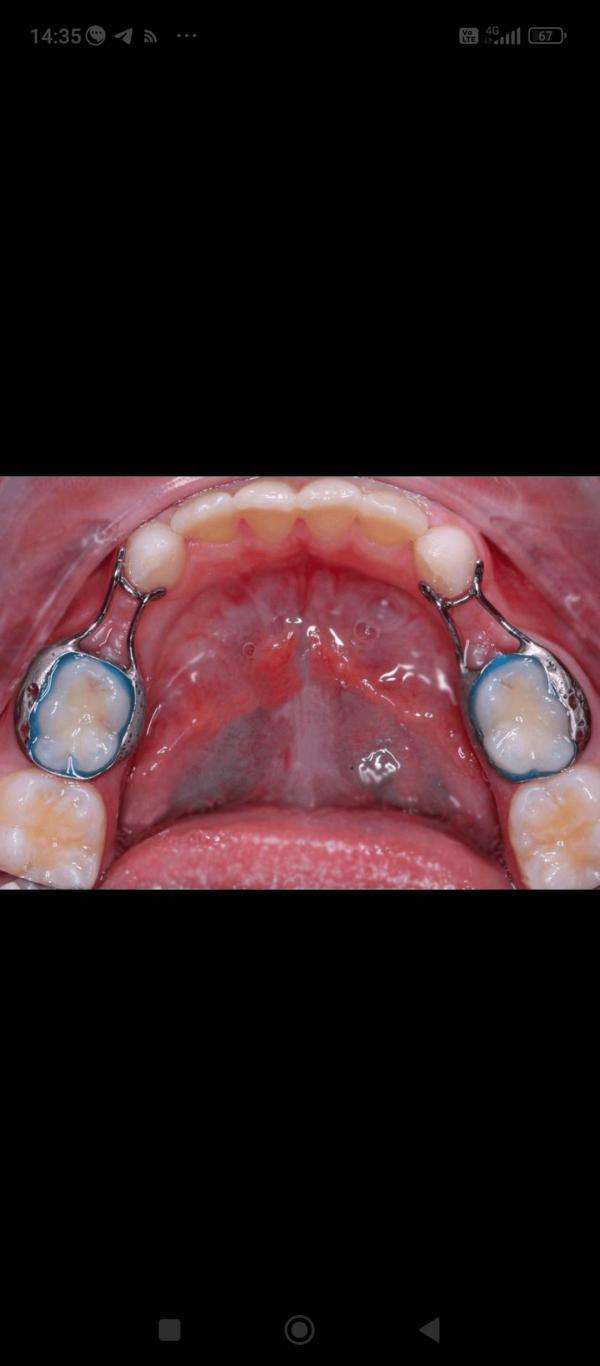

Кто-нибудь ставил кольцо типа такого? Поделитесь своими случаями. Фото из интернета. У нас такая же ситуация, только с одной стороны. Отсутствует четвёрка. Вот не знаю так уж ли надо ставить эту железку на молочный зуб. Да и 15тыс не лишние

У моего сына стоит, нельзя терять место для будущего зуба

Зачем вам смещение других зубов в будущем? Мы ходим с такой распоркой.